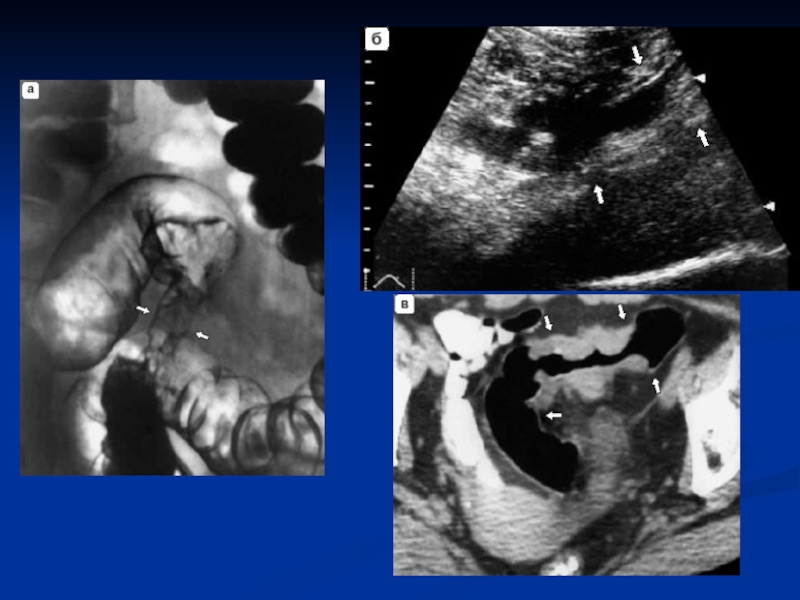

Слайд 20Диагностика

Объективное исследование: осмотр, пальпация, аускультация, ректальное исследование.

Ирригоскопия (контрастное исследование толстой кишки с барием) (локализация, протяженность опухоли и ее размеры).

КТ и УЗИ, сцинтиграфия печени ( для исключения метастазов в печени).

Слайд 22УЗИ. Метастазы печени.

УЗИ. Метастазы печени.